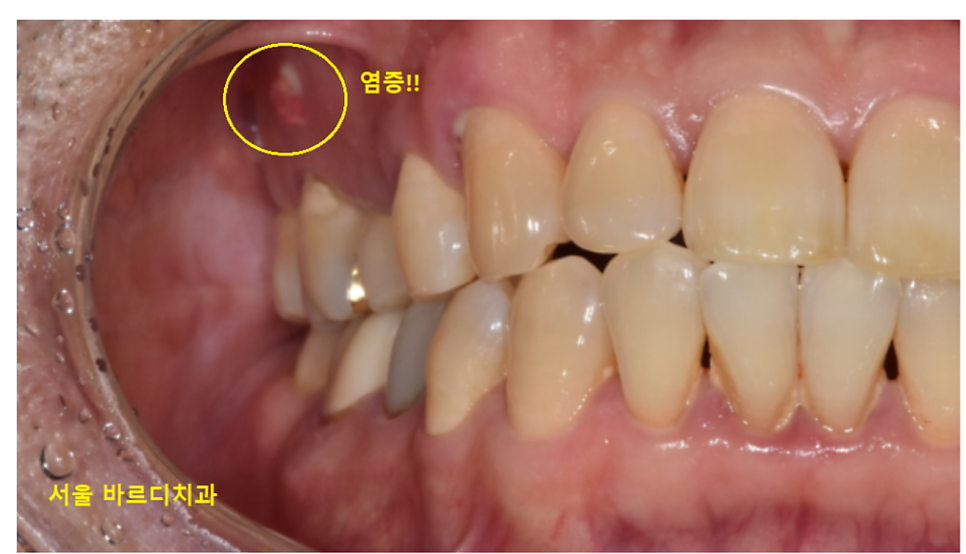

여드름처럼 부풀지는 않으셨나요~?

이렇게 말이죠!

뾰루지가 나타날 수도 있고

치아 주변이 부어있을 수도 있습니다.